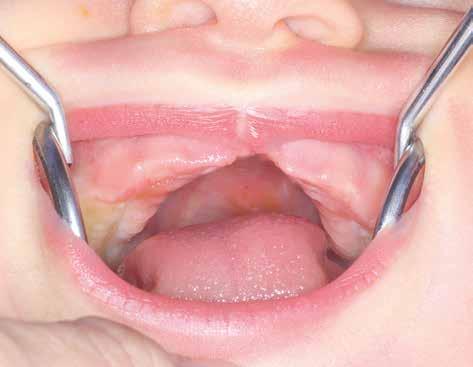

Obr. 1.2 Pravostranný rozštěp horního rtu ve formě zářezu a strukturální poruchy oblasti retní červeně a horního rtu – je naznačena lehká deformace nosního křídla vpravo, nosní vchod není porušen (archiv oddělení ortodoncie a rozštěpových vad

Stomatologické kliniky FNKV Praha)

Obr. 1.3 Pravostranný rozštěp rtu a alveolárního výběžku horní čelisti zasahující od nosního vchodu po foramen incisivum (primární patro) – kontinuita nosního vchodu je přerušená, nosní křídlo na straně rozštěpu kolabuje (archiv oddělení ortodoncie a rozštěpových vad